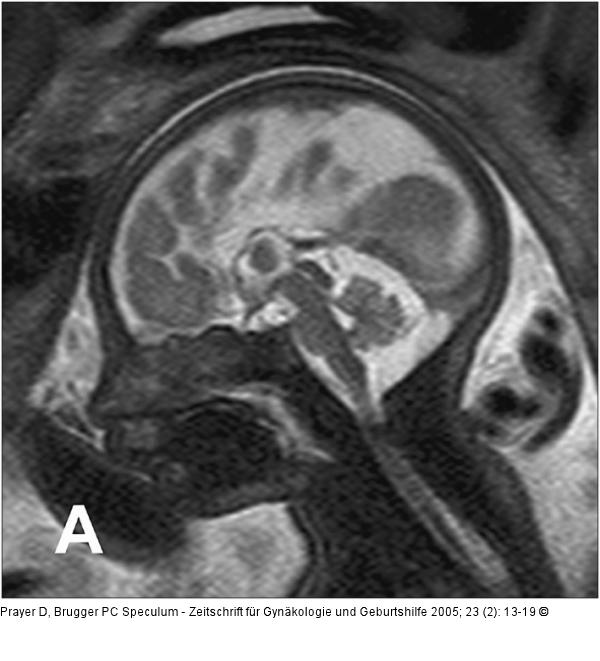

Abbildung 2a-b: Pränatale Magnetresonanztomographie SSW 30, Fetus mit Balkenagenesie, A. Medianes Schnittbild: Fehlender Balken, radiäre Gyrierung an der Medialfläche der Hemisphäre. Der Aquädukt und die Vierhügelplatte unauffällig. Der Hirnstamm zeigt dorsal dünklere Signale als ventral, was der normalen, dort bereits in dieser SSW vorhandenen Myelinisierung entspricht. Im Profil geringe Retrognathie. B. Frontales Schnittbild. Typische Konfiguration der Seitenventrikel, die auf Grund der medial der Vorderhörner erkennbaren Probst’sche Bündel weit auseinander stehen. In den erweiterten Temporalhörnern erkennt man eine nahezu senkrecht stehende Hippocampusformation, was einer Malrotation entspricht. Die Gyrierung ist symmetrisch, eine pathologische Konfiguration des frontalen Anteils des Gyrus cinguli, wie sie im Rahmen der Balkenagenesie zu erwarten ist, besteht. Intrazerebral ist die zelldichtere und daher dünklere Stammganglienregion von der helleren weißen Substanz, die ebenfalls in entwicklungsbedingt unterschiedliche Graustufen gegliedert ist, abgrenzbar. |

SSW 30, Fetus mit Balkenagenesie, A. Medianes Schnittbild: Fehlender Balken, radiäre Gyrierung an der Medialfläche der Hemisphäre. Der Aquädukt und die Vierhügelplatte unauffällig. Der Hirnstamm zeigt dorsal dünklere Signale als ventral, was der normalen, dort bereits in dieser SSW vorhandenen Myelinisierung entspricht. Im Profil geringe Retrognathie. B. Frontales Schnittbild. Typische Konfiguration der Seitenventrikel, die auf Grund der medial der Vorderhörner erkennbaren Probst’sche Bündel weit auseinander stehen. In den erweiterten Temporalhörnern erkennt man eine nahezu senkrecht stehende Hippocampusformation, was einer Malrotation entspricht. Die Gyrierung ist symmetrisch, eine pathologische Konfiguration des frontalen Anteils des Gyrus cinguli, wie sie im Rahmen der Balkenagenesie zu erwarten ist, besteht. Intrazerebral ist die zelldichtere und daher dünklere Stammganglienregion von der helleren weißen Substanz, die ebenfalls in entwicklungsbedingt unterschiedliche Graustufen gegliedert ist, abgrenzbar. |